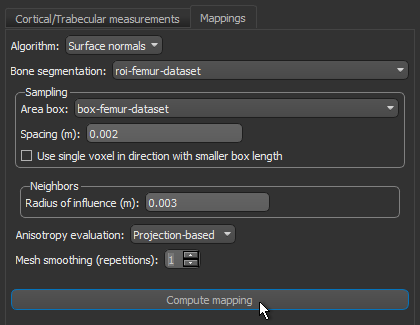

- Do the following on the Mappings tab:

- Choose Surface normals in the Algorithm drop-down menu.

- Choose the region of interest that you created for this tutorial in the Bone segmentation drop-down menu.

- Choose the box that encloses the area that you want to include in your analysis in the Area box drop-down menu.

- Enter a value of 0.002 m in the Spacing edit box.

NOTE Although the highest resolution, or lowest spacing, of the tutorial dataset is 0.5 mm, this should be increased to 2.0 mm if the entire 3D shape of the femur will be mapped.

- Select a value between 1 and 3 mm in the Radius of influence edit box.

NOTE The radius of influence defines the kernel size, or elementary volume, within which anisotropy will be evaluated. You should note that a too small radius of influence may result in a low signal-to-noise ratio, while a too high radius can result in averaging and edge effects.

- Choose Projection-based in the Anisotropy drop-down menu.

- Choose a number of iterations in the Mesh smoothing (repetitions) spin box, optional.

- Click the Compute Mapping button.